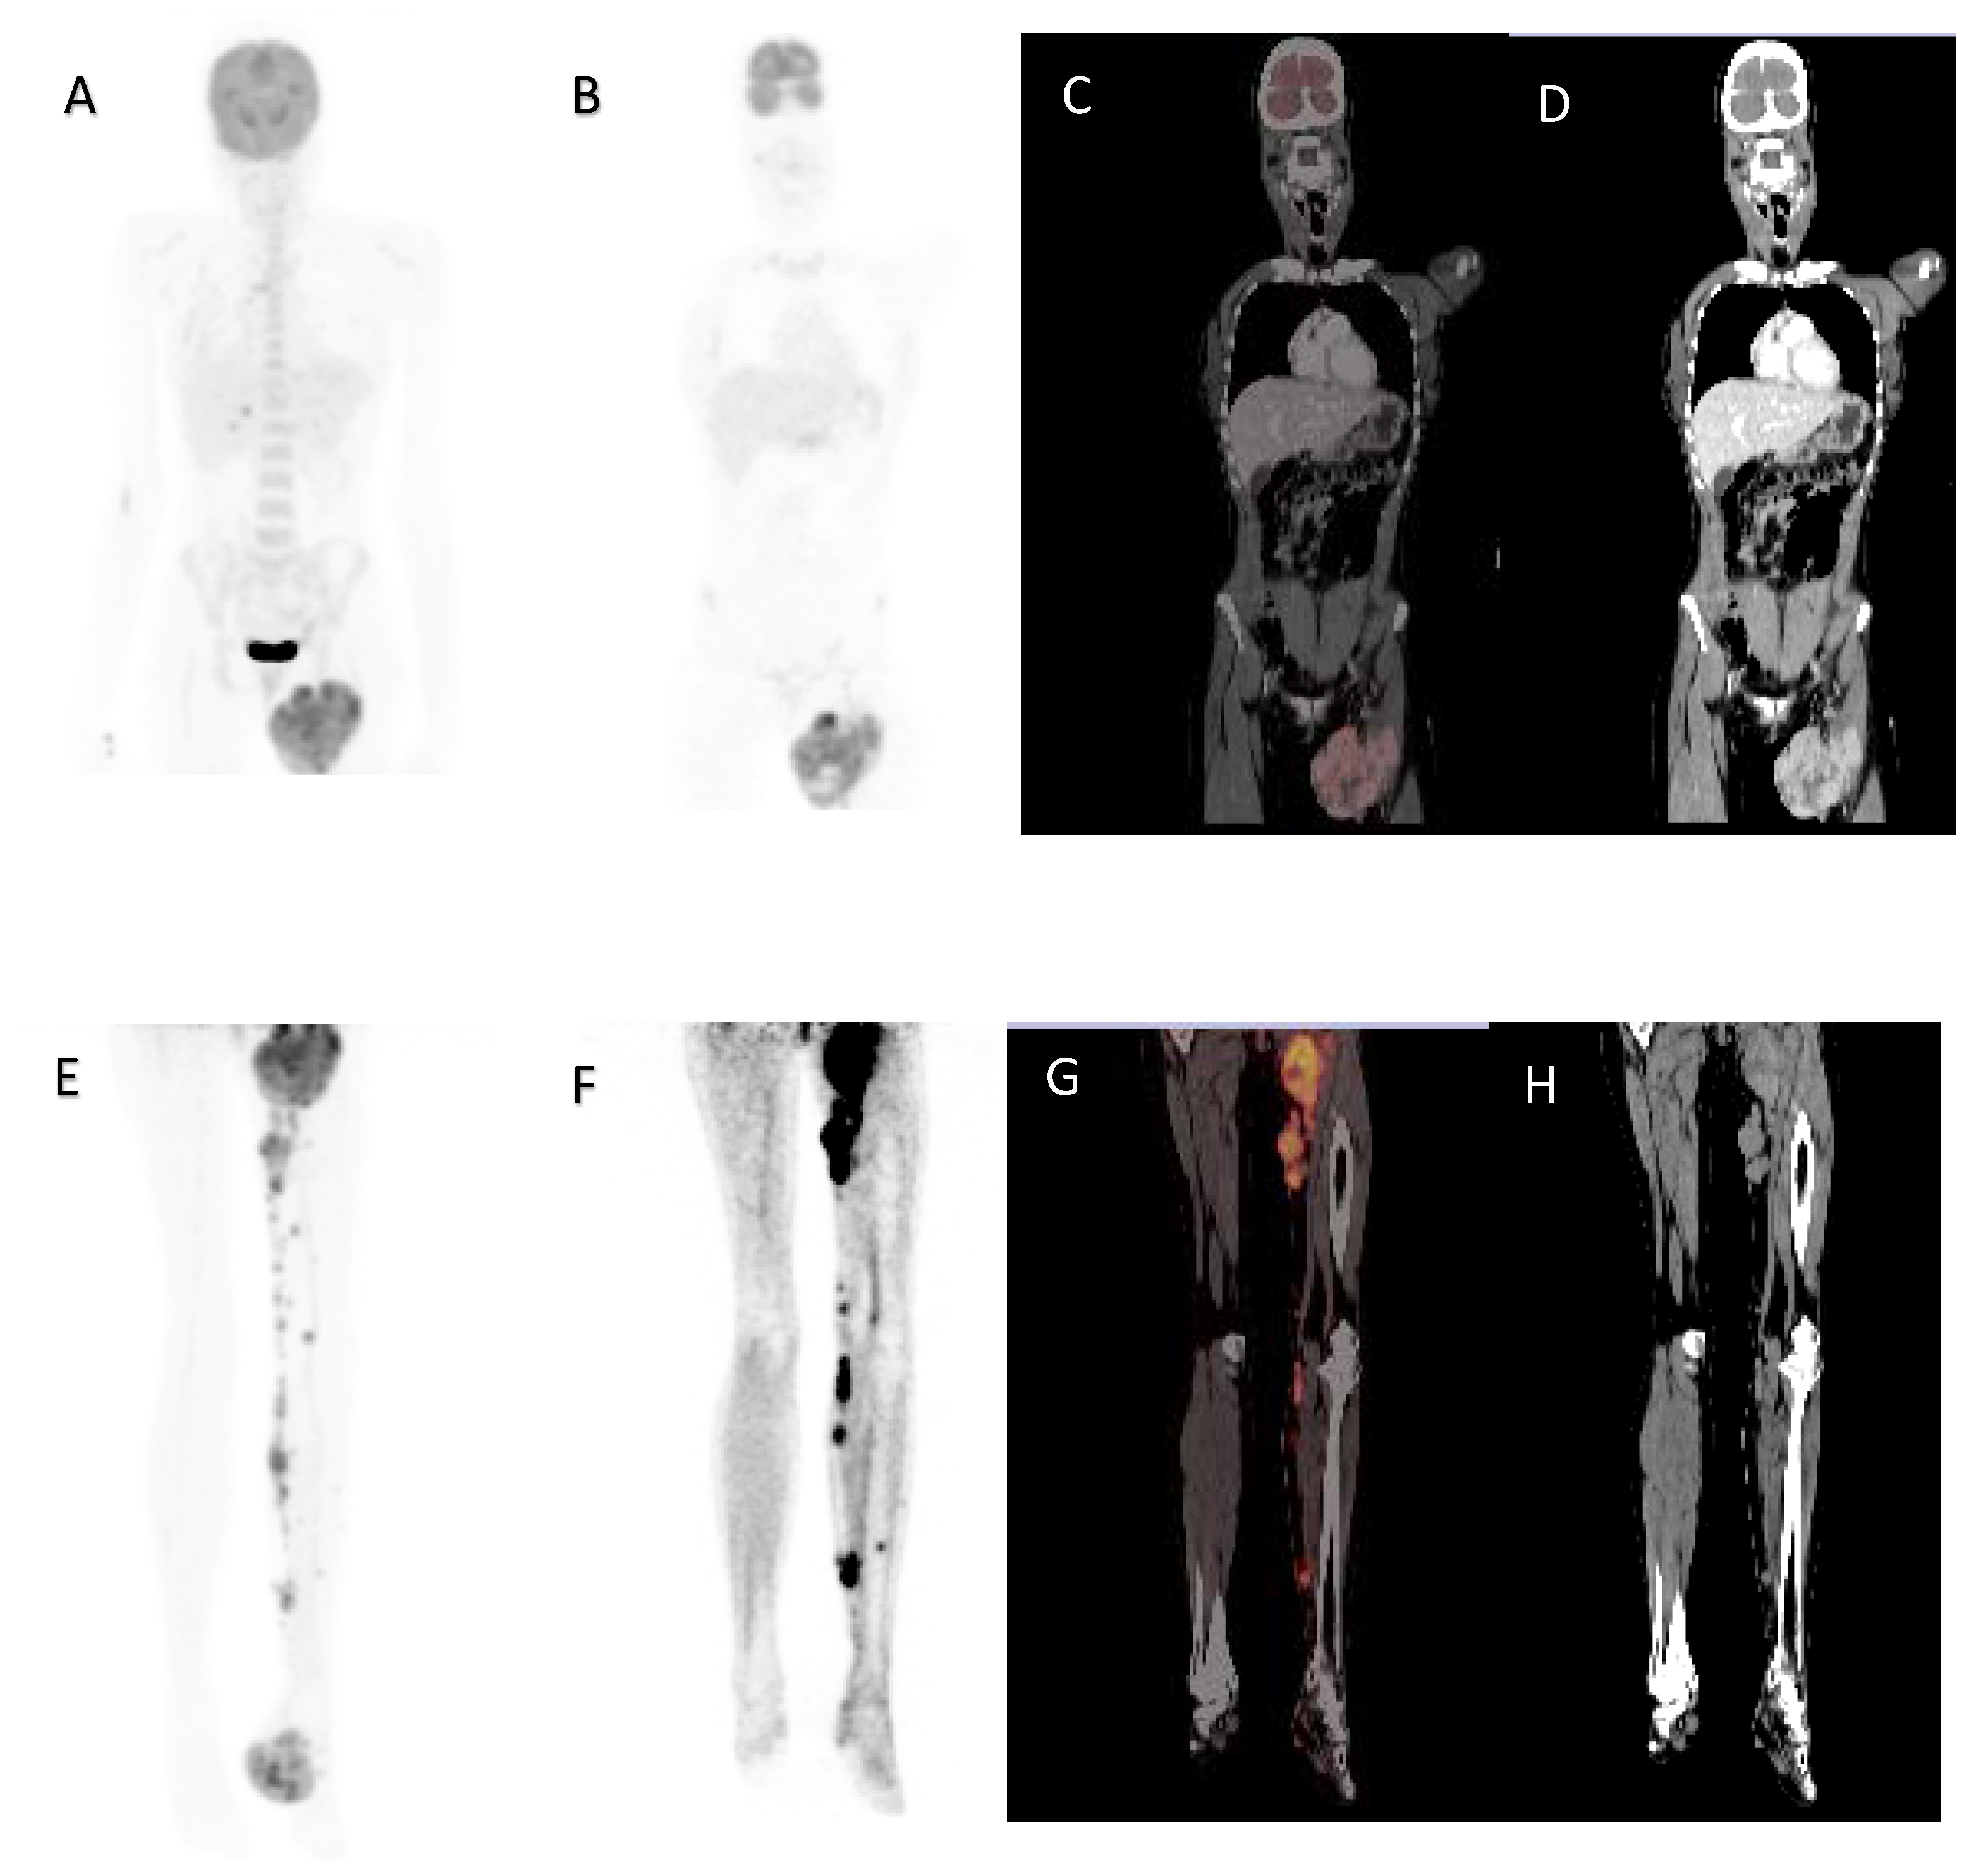

Figure 4.

A 32-year-old female, acral lentiginous melanoma resected from the left foot, presented with a recurrence and nodal metastases. Maximal intensity projection image (A), coronal 18F-FDG PET (B), fused (C) and CT (D) images demonstrating large inguinal node metastases. Maximal intensity projection image (E), Coronal 18F-FDG PET of lower limbs (F), fused (G) and CT (H) images demonstrating left foot primary with subcutaneous and nodal metastases in the left leg. MTV 126.73 cm3, TLG 567.75, SUVmax 10.78, whole-body MTV 635.48 cm3 and whole-body TLG 9964.33. Overall survival was 8 months.